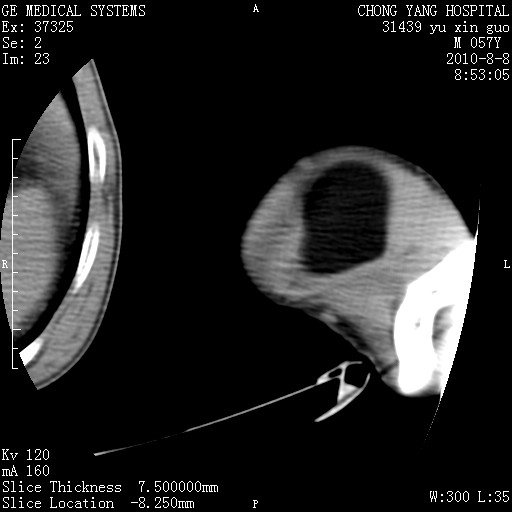

标题: CT28267:M57Y 上臂包块8年余。 [打印本页]

标题: CT28267:M57Y 上臂包块8年余。

包膜光滑、完整的脂肪密度肿块,支持脂肪瘤。

脂肪瘤。有ct值?